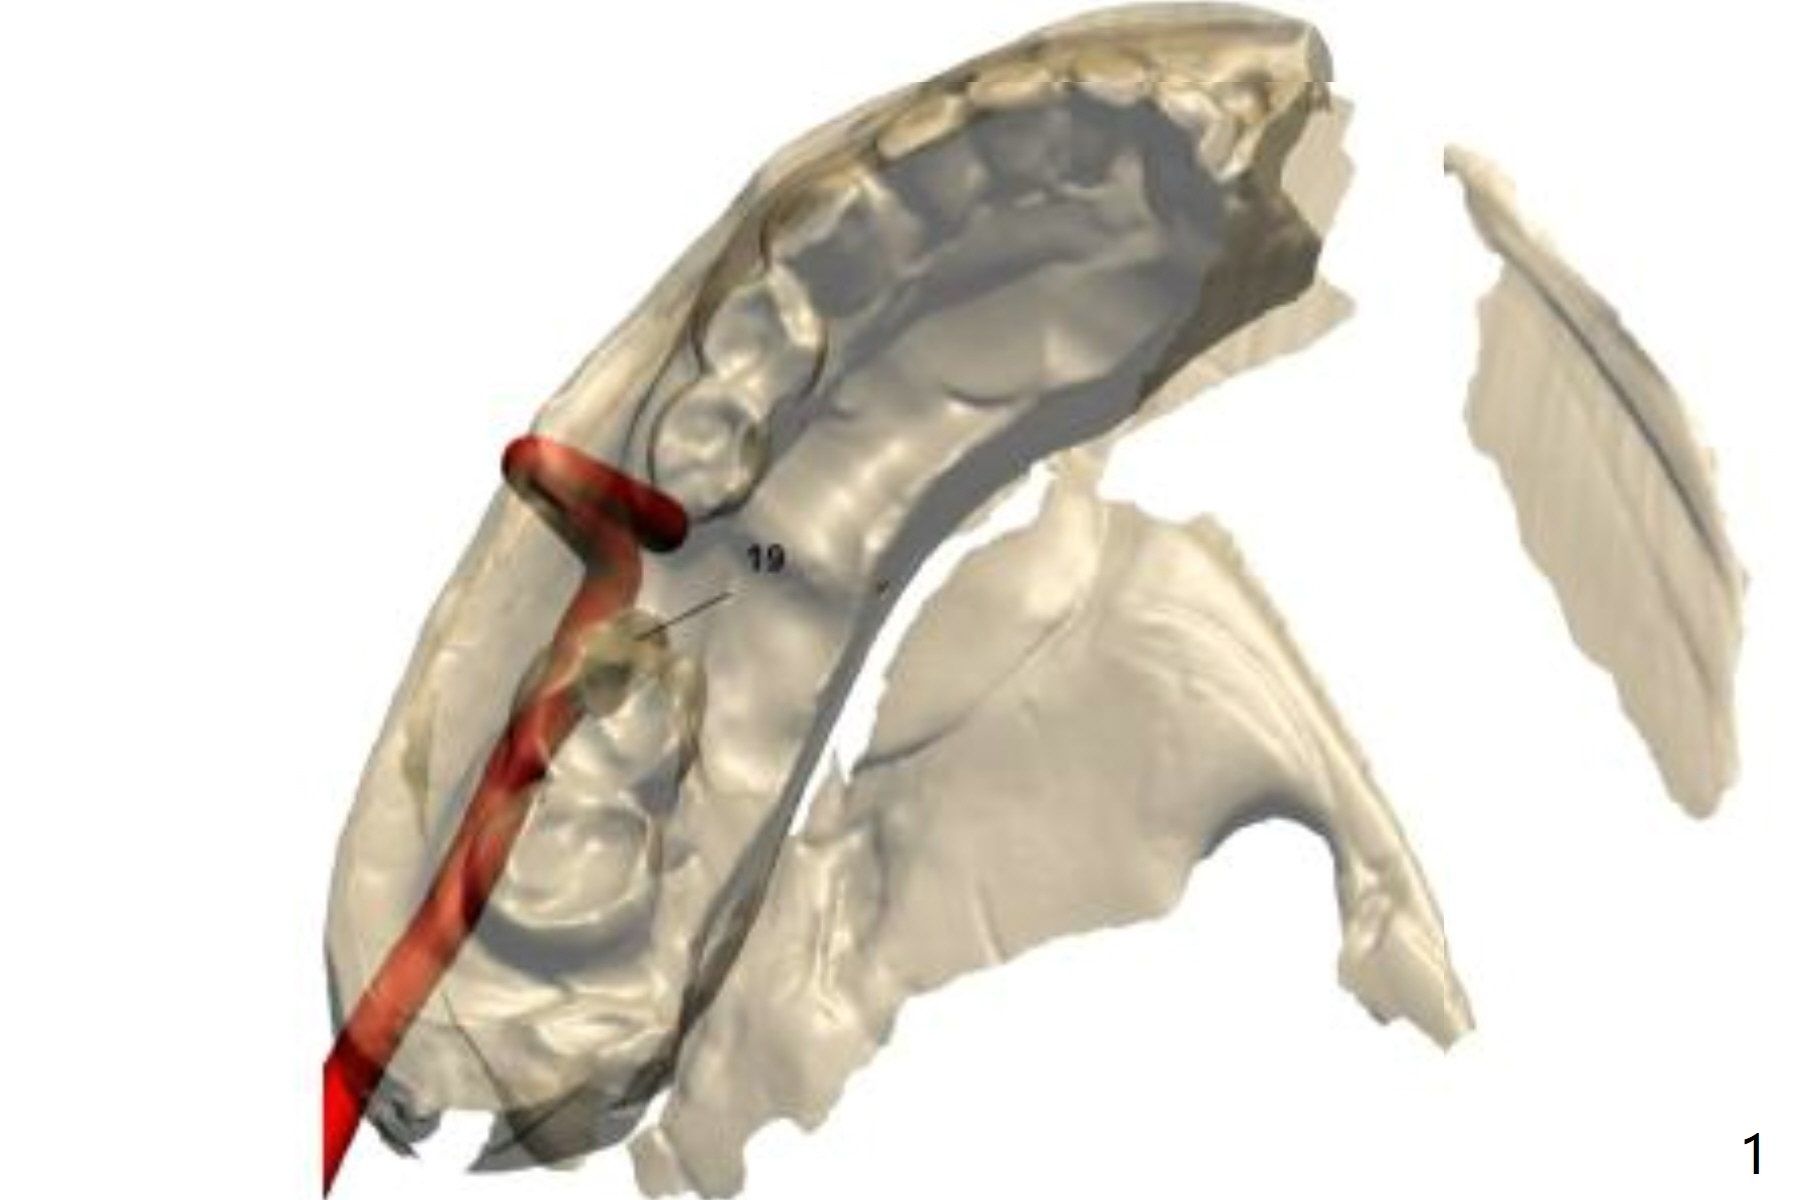

After cementation of an implant crown at #15, a 62-year-old man requests an implant at #19 to replace a RPD. Instead of 1-piece implant, a 2-piece one is chosen (Fig.1-3).